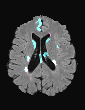

In recent years, data-driven machine learning (ML) methods have revolutionized the computer vision community by providing novel efficient solutions to many unsolved (medical) image analysis problems. However, due to the increasing privacy concerns and data fragmentation on many different sites, existing medical data are not fully utilized, thus limiting the potential of ML. Federated learning (FL) enables multiple parties to collaboratively train a ML model without exchanging local data. However, data heterogeneity (non-IID) among the distributed clients is yet a challenge. To this end, we propose a novel federated method, denoted Federated Disentanglement (FedDis), to disentangle the parameter space into shape and appearance, and only share the shape parameter with the clients. FedDis is based on the assumption that the anatomical structure in brain MRI images is similar across multiple institutions, and sharing the shape knowledge would be beneficial in anomaly detection. In this paper, we leverage healthy brain scans of 623 subjects from multiple sites with real data (OASIS, ADNI) in a privacy-preserving fashion to learn a model of normal anatomy, that allows to segment abnormal structures. We demonstrate a superior performance of FedDis on real pathological databases containing 109 subjects; two publicly available MS Lesions (MSLUB, MSISBI), and an in-house database with MS and Glioblastoma (MSI and GBI). FedDis achieved an average dice performance of 0.38, outperforming the state-of-the-art (SOTA) auto-encoder by 42% and the SOTA federated method by 11%. Further, we illustrate that FedDis learns a shape embedding that is orthogonal to the appearance and consistent under different intensity augmentations.